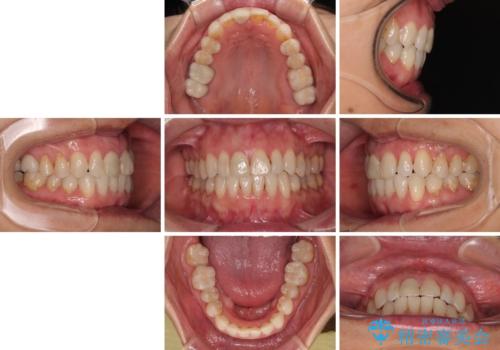

矯正治療後に銀歯をセラミッククラウンなどに置き換えていくと、どうしても後戻りを起こしてしまうため、矯正治療が概ね終了した時点で銀歯を全てセラミックとし、最後に仕上げでインビザラインにを用いて細かいデコボコを改善していくこととしました。

とても明るい口元となり、人目を気にせず、大きく口を開けて笑えるようになりました。